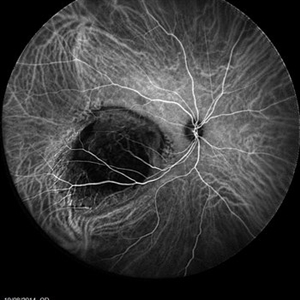

An ICG Angiography photography of a 27-year-old woman with a choroidal tumor in her right eye.

Photographer: Avris Romario Diparaja Siahaan, Klinik Mata Nusantara

Imaging device: Heidelberg Spectralis

Condition/keywords: choroidal tumor, indocyanine green (ICG) angiography, ultra-wide field imaging